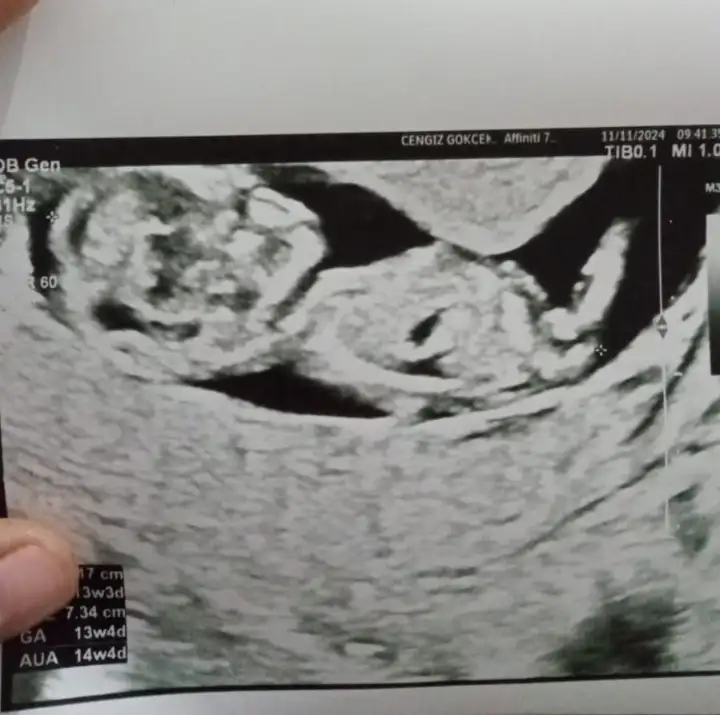

Banada bakabilirminiz 13 haftalık

• IMG_20241117_072114.webp

IMG_20241117_072114.webp

20,7 KB · Görüntüleme: 50

Bana da bakar mısınız sanki çıkıntı yukarı çıkıyor gibi erkeğe benzettim ama düz de değil tam. Daha erken mi acaba kafa yapısı erkek gibi

Eklentiler

• IMG_5349.webp

IMG_5349.webp

48,4 KB · Görüntüleme: 52

• IMG_5348.webp

IMG_5348.webp

30 KB · Görüntüleme: 46

• IMG_5347.webp

IMG_5347.webp

30,3 KB · Görüntüleme: 51